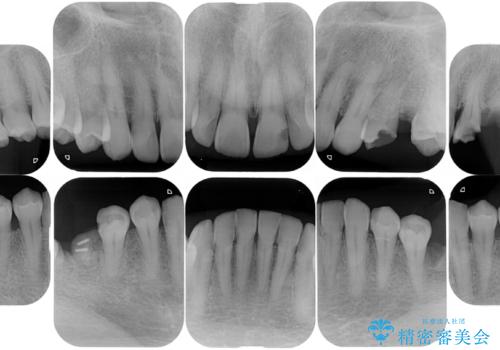

- リタイアを期に海外に移住されることになり、出発前に全顎的に治療をしておきたいと来院された患者様です。最短期間で治療を終了できるよう、事前に綿密な計画を立てたうえで集中的に治療を行いました。

期日が決まっていたため、それぞれの処置にかかる日数・時間を綿密に計算したうえで短期間での集中治療を行いました。毎回の処置時間を長めに設定し、1回の来院でより多くの処置を行えるようにしたおかげで全顎的な治療も短期間で仕上げることができました。